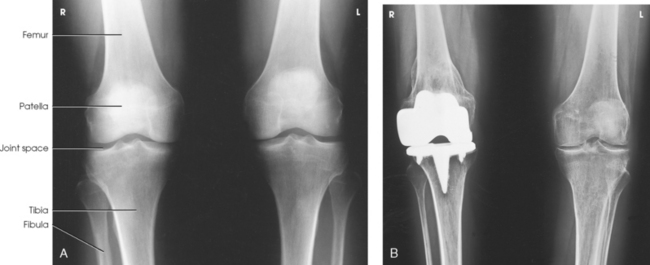

Leach et al.1 recommended that a bilateral weight-bearing AP projection be routinely included in radiographic examination of arthritic knees. They found that a weight-bearing study often reveals narrowing of a joint space that appears normal on a non–weight-bearing study.

Structures shown: The resulting image shows the joint spaces of the knees. Varus and valgus deformities can also be evaluated with this procedure (Fig. 6-128).